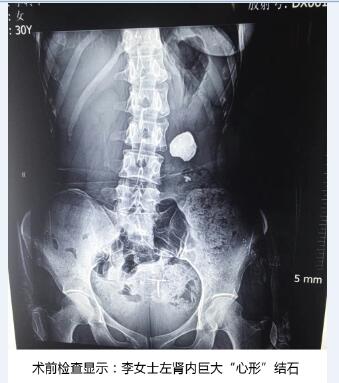

谈起过去这一年,三十岁的李女士唏嘘不已。多年前公司体检时发现左肾有轻微多发肾结石。十年来,因为没痛没痒的,她就没在意,存有侥幸心理,认为平时多运动,多喝一些水,注意饮食清淡,就可以把结石排出去。直到半个月前,她感到左腰部时常有剧烈的胀痛感,经常反复高烧,出现血尿、感染症状,且越来越重。到医院检查,检查结果着实把给她和专家们吓坏了,B超检查报告显示李女士左肾内结石几乎充满了整个肾,形似一颗“心形”。为了取出结石、保住左肾,她在家乡奔走求医,寻访多家大型医院,都告诉她需做1-2次开放手术,且没法保证取净结石。最终她通过朋友打听到天津百信医院,并抱着极大希望赶到该院。

天津百信医院接诊了该患者,经检查发现,患者左肾肾盂充满了结石,直径达到5.5cm,结石几乎充满整个肾体,犹如一颗硕大的“心形”,并发左肾重度积水,左肾随时有坏死可能!